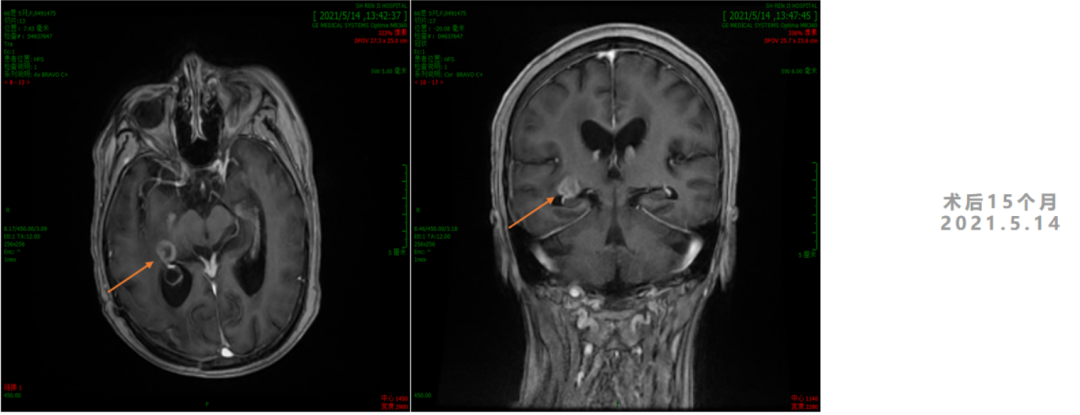

3. 2021年3月18日,2021年3月起,患者诉左侧肢体乏力,需搀扶行走。影像学检查显示,右侧脑室后角旁见结节样环形强化灶,直径7-8mm。MRS:NAA峰可见下降,Cho峰升高。Cho/Cr为0.748,Cho/NAA为2.13,考虑肿瘤复发可能。患者行射波刀治疗(24Gy/4FX),TMZ+安罗替尼2周期,TTFields重新定位,电场治疗调整贴片位置。